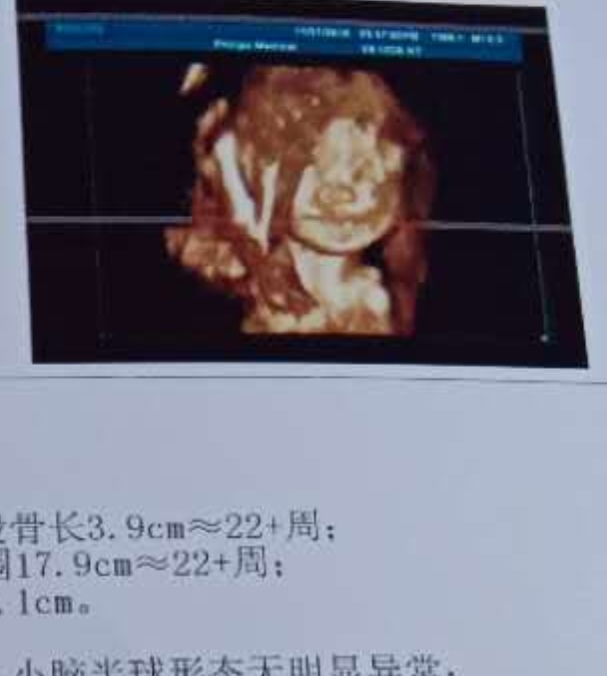

宝宝2个月30天